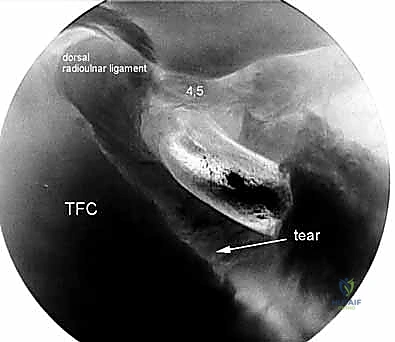

2. The 4-5 Portal

- Location: Situated between the fourth and fifth dorsal extensor compartments.

- Anatomy:

- Fourth Compartment: Extensor digitorum communis (EDC) tendons.

- Fifth Compartment: Contains the extensor digiti minimi (EDM) tendon.

- Neurovascular Risks: Similar to the 3-4 portal, generally safe, but transverse branches of the dorsal cutaneous branch of the ulnar nerve can be in proximity. Again, blunt dissection is key.

- Function: A crucial viewing portal for the ulnocarpal joint and for introducing instruments to address ulnar-sided pathology, particularly TFCC tears.

Dorsal Distal Radioulnar Joint (DRUJ) Portals

These portals offer direct access to the DRUJ for assessing its articular cartilage and ligaments.

1. The Dorsal Radioulnar Joint Portal (Proximal and Distal)

- Location: Lies between the ECU and the EDM tendons. There can be a proximal (PDRUJ) and a distal (DDRUJ) portal.

- Anatomy: The interval between the fifth (EDM) and sixth (ECU) extensor compartments.

- Neurovascular Risks: Transverse branches of the dorsal cutaneous branch of the ulnar nerve are the only sensory nerves in proximity, typically at a mean of 17.5 mm distally (range 10–20 mm) from the portal. Careful dissection is still advised.

- Function: Used in concert with the volar distal radioulnar portal to fully assess the articular cartilage of the ulnar head and sigmoid notch, and for instrumentation within the DRUJ.